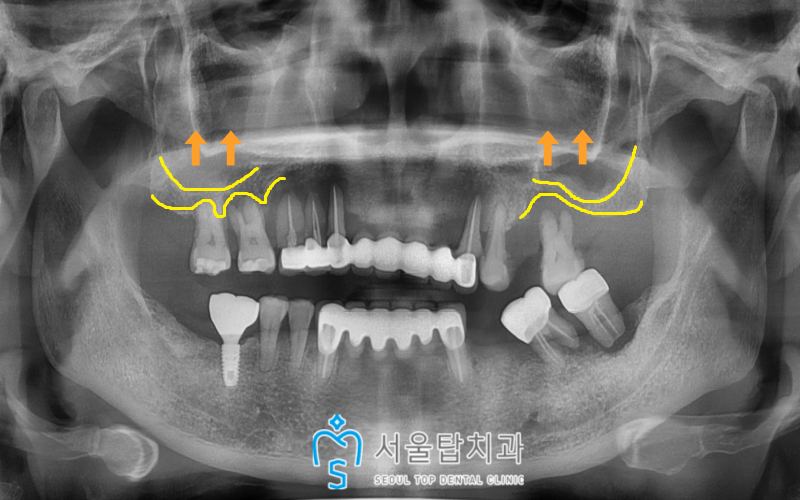

식립전 구강 내 상황을 체크해보니

위턱 양측 어금니 부위에는

상악동이 많이 내려와 있고

치조골이 많이 부족하여

상악동 거상술을 동반한

임플란트 식립이 필요하였는데요.

특히 양측 첫번째 큰 어금니 부위가

치조골이 부족한 상황으로,

상악동 거상술 후 치유 기간을 충분히 가지고

임플란트 식립이 필요하였습니다.